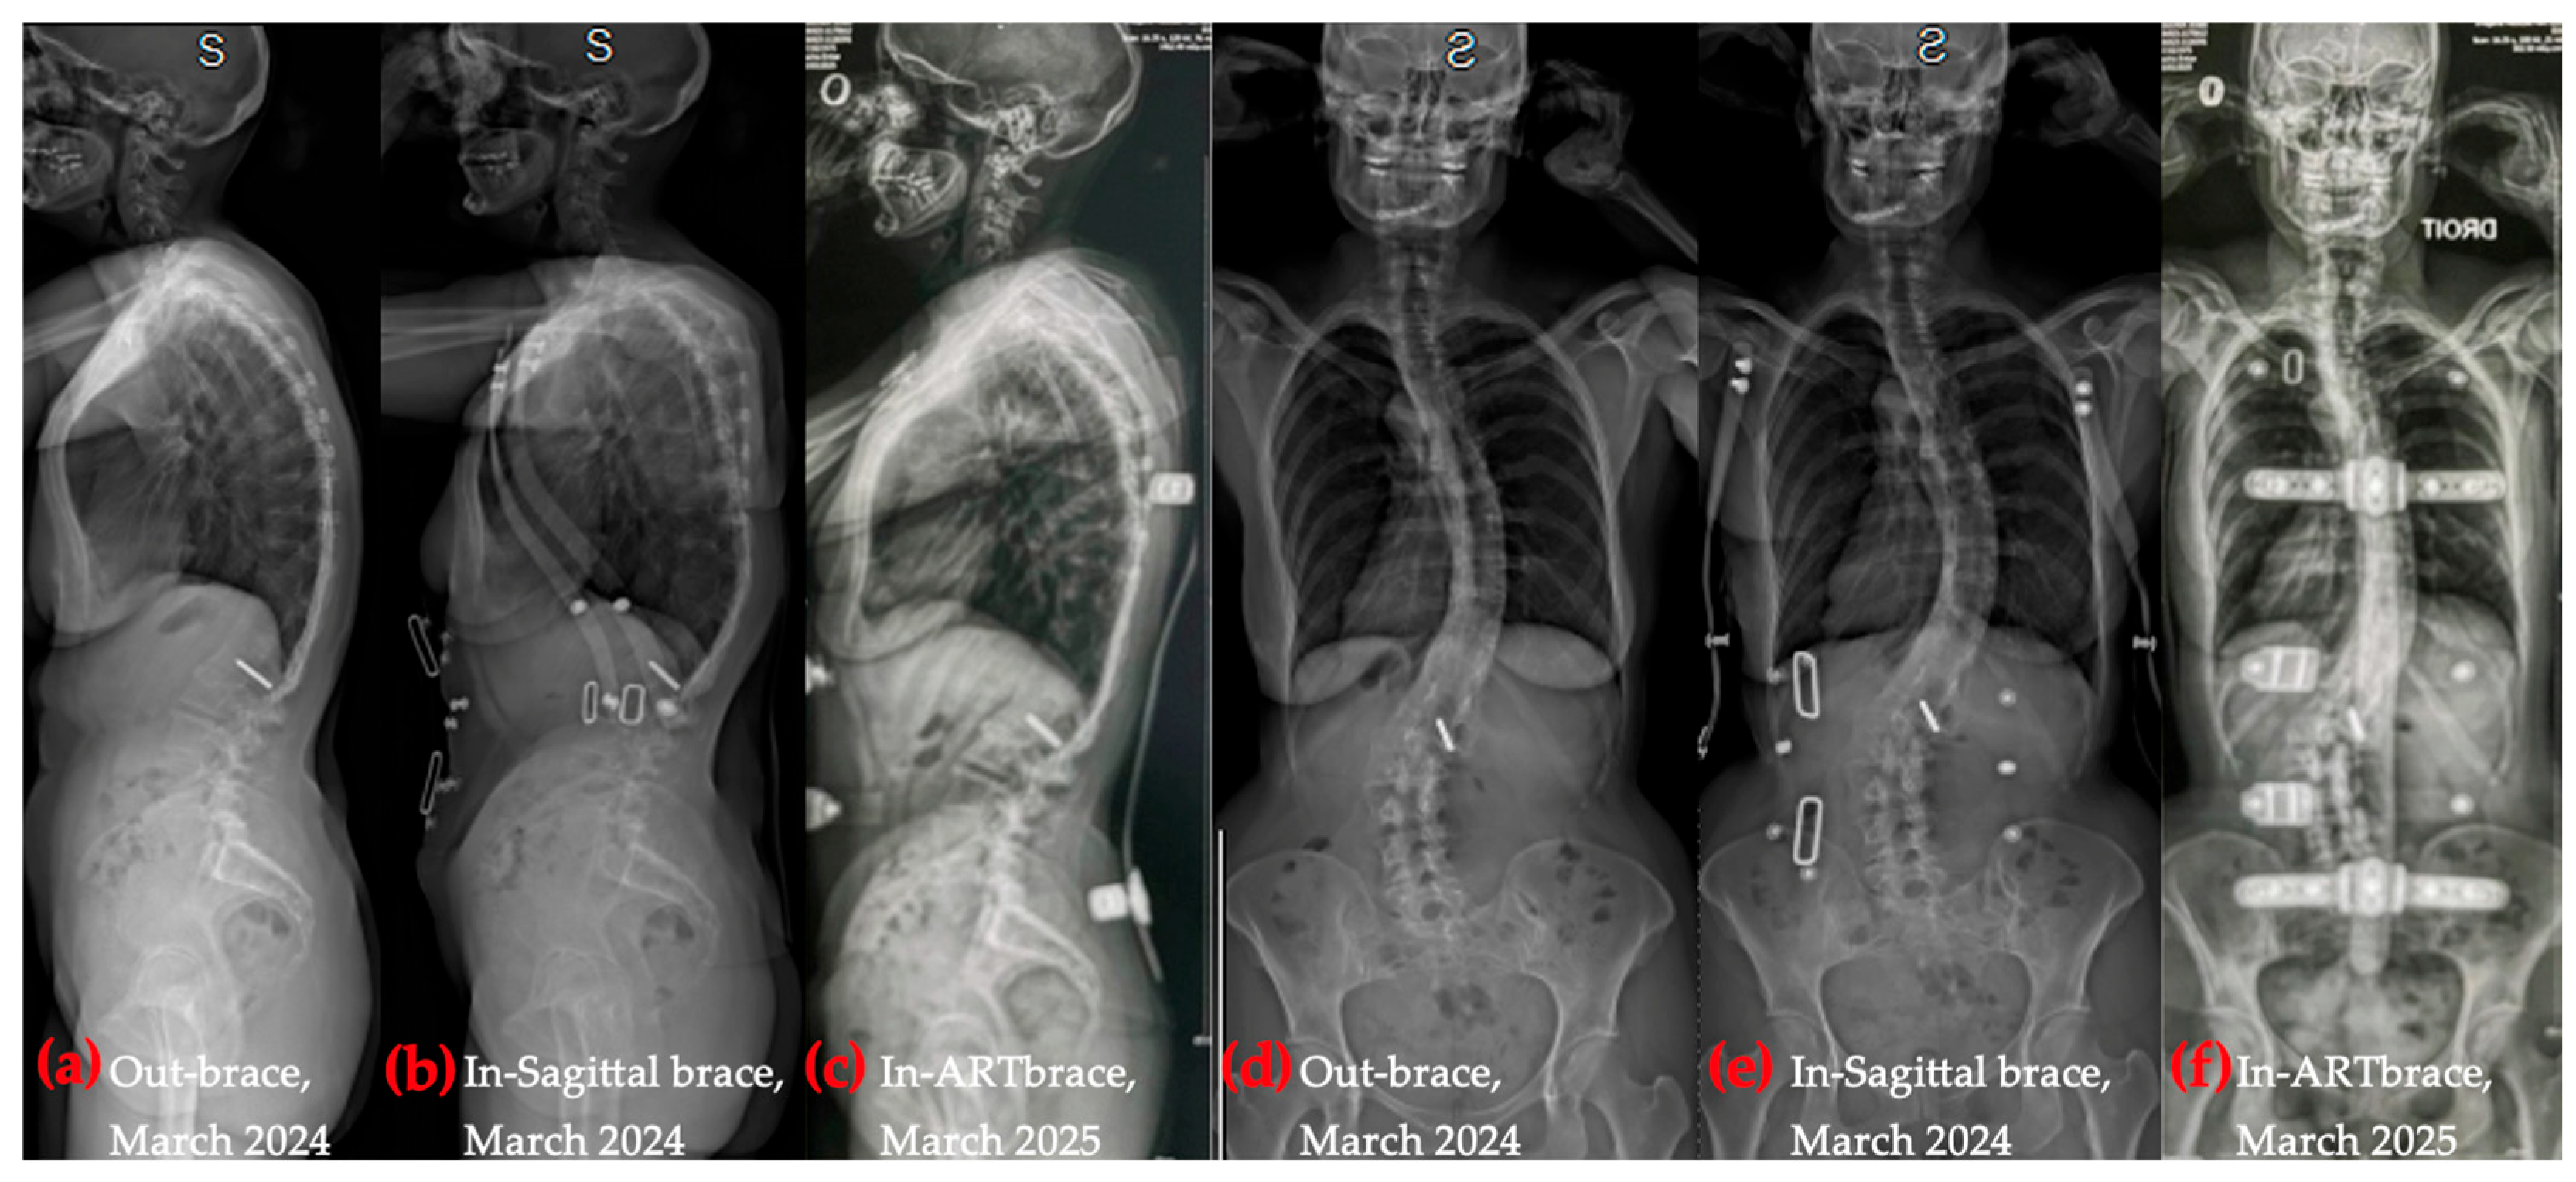

4.1. Structural Realignment and Sagittal Correction

4.2. Coronal Alignment and Rib Cage Remodeling